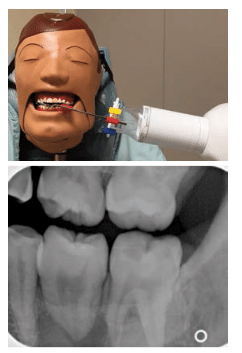

Cone Cut X Ray. Three simple rules serve to identify and correct any errors. If the image is foreshortened or elongated adjust the tube angle. Cone cut may be caused by. If you cut the target off at the edge of the beam cone cut simply move the beam over toward the area of cone cut.

In cone beam CT a divergent cone-shaped source of radiation is directed through the target. Hence the collimator which reduces the size and shape or cross-sectional area of the X-ray beam doesnt completely exposes the film resulting in cone cut. Medical Dictionary for the Dental Professions Farlex 2012 Want to thank TFD for its existence. Phalangioma The term phalangioma was used by Dr. The attenuated x-rays are detected on the opposite side by an x-ray detector which has multiple dexels in the x and y-axis 2. Simply put your environment will be made invisible so that you can instantly spot important ores even from a great distance.

Bitewings show teeth above the gum line and the height of the bone between teeth. The shape of the cone-cut depends on the type of collimator used when exposing the receptor. This angulation is derived from the average vertical angulation of the maxillary and mandibular teeth when in occlusion and allows the x-rays to strike the film at a 90 degree angle providing the most accurate representation of the teeth on the film with maximal overlap of the buccal and lingual alveolar crests and cusps of the teeth. The most common being the image receptor is not in line with the position indicating device PIDradiographic coneHence the collimator which reduces the size and shape or cross-sectional area of the X-ray beam doesnt completely exposes the film resulting in cone cut. Round Cone Cut Rectangular Cone Cut.

Projection errors PID alignment artifact If the PID is misaligned and the x-ray is not centered over the film a partial image is seen on the resultant radiograph this partial image is called cone-cut. The shape of the cone-cut depends on the type of collimator used when exposing the receptor. This results from the x-ray beam not positioned perpendicular over the film. This is uncomfortable for the patient and may produce an inadequate view of the teeth and surrounding bone. Three simple rules serve to identify and correct any errors.

Cone cut may be caused by. Receptor instruments with beam guides facilitate beam centering over the receptor when properly assembled. Cone cut may be caused by various reasons. From now on no more annoying cave expeditions are necessary. This type of error is termed a cone cut Placing the posterior Rinn assembly into the incorrect quadrant causes the rod to get caught on the cheek and doesnt allow the assembly to be positioned correctly into the mouth.

When using digital imaging the cone-cut appears as an opaque or white area. Receptor instruments with beam guides facilitate beam centering over the receptor when properly assembled. If you cut the target off at the edge of the beam cone cut simply move the beam over toward the area of cone cut. Cone cut errors are caused by not centering the x-ray beam over the receptor. PDF In routine dental radiography one may encounter numerous radiographic errors one of which may be partial images or cone cuts.

Cone cut errors are caused by not centering the x-ray beam over the receptor. Cone cut may be caused by. This is uncomfortable for the patient and may produce an inadequate view of the teeth and surrounding bone. Cone-beam computed tomography systems CBCT are a variation of traditional computed tomography CT systems. If you cut the target off at the edge of the beam cone cut simply move the beam over toward the area of cone cut.